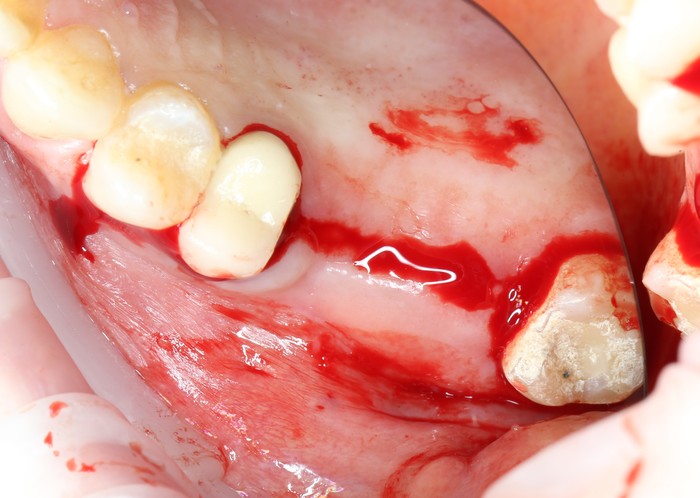

После того, как анестезия подействовала, при помощи скальпеля производится разрез, а распатора — скелетирование кости (отделение надкостницы от компактного вещества кости).

Разрез:

Скелетирование кости: